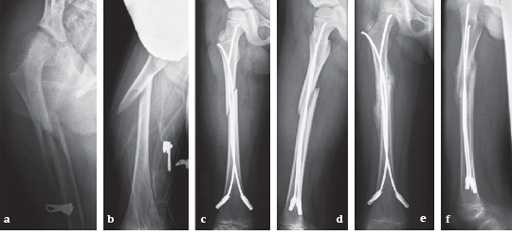

(provided by Steffen Berger and Theddy F Slongo, Bern, CH)

Fracture of the right femoral shaft (32-D/5.2) in a 8-year-old boy.